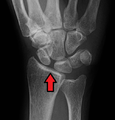

Stress view showing scapholunate instability